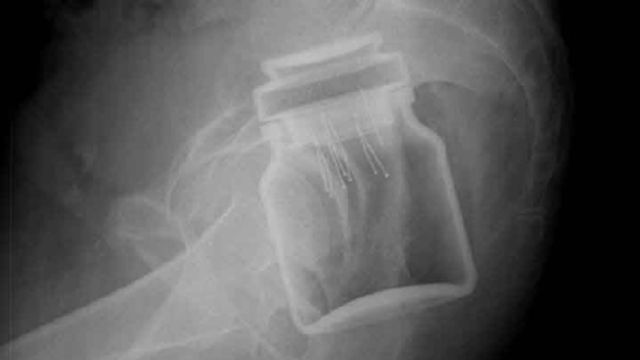

Barattoli di caffè istantaneo, deodoranti, chiodi, monete e persino sex-toys: ecco cosa può "nascondersi" all'interno di un paziente che si reca in Pronto Soccorso

Barattoli di caffè istantaneo, deodoranti, chiodi, monete e persino sex-toys. Ecco cosa può "nascondersi" all'interno di un paziente che si reca in Pronto Soccorso. A mostrarlo sono le divertenti immagini di alcune radiografie pubblicate da un sito specializzato, radiopaedia.org. Inizialmente dedicato ai radiologi, il portale è diventate un fenomeno virale con una media di sette milioni di visitatori al mese.